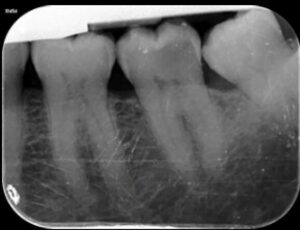

Abbildung 2: Die präoperative intraorale Röntgenaufnahme von Zahn 37 zeigt die bis an die Pulpa angrenzende distale Ausdehnung der kariösen Läsion.